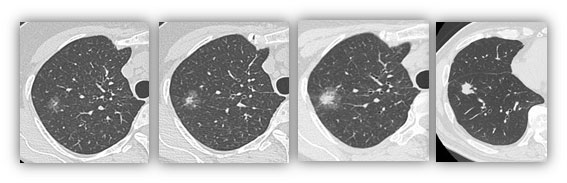

近年、検診CTの普及で早期肺がんが多く発見されるようになりました。図に肺がんの胸部CTを示しますが、淡い影(すりガラス)と濃い白い部分(中心部分)が混在しています。中心部分の割合が多いほど悪性度が高いことがわかっています。肺がんで重要なのはリンパ節転移の有無です。一般に、リンパ節転移がないのであれば、他の臓器に転移の可能性は非常に低くなります。このようながんを画像的非浸潤がんと命名しています。これまでの研究から、中心部分の割合が全体の25%までと定義されています。図では左の2つのCTまでが画像的非浸潤がんにあたります。画像的非浸潤がんの条件を満たした肺癌に対しては、基本的に部分切除を適応させています(中枢病変は例外)。当科ではさらに、リピオドールマーキングを併用した肺部分切除を行っています。

次に、車いすで手術室に移動して手術を行います。手術中はレントゲンに写った造影剤をすべて切り取ることで腫瘍も一緒に切除されてきます(下図2)。そもそも、早期がんに対する部分切除を行うためには腫瘍の局在を確認する必要があります。これまでは直接触ることで腫瘍を確認していたため、傷が大きくなってしまいました。しかし、この方法では腫瘍を触る必要がありませんので、最小限の傷で手術を行うことができます。当科では2㎝の傷1つと5mmの傷2つを基本としています。